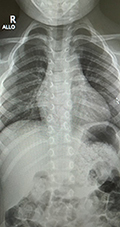

A veleszületett gerincferdülés tekintetében

Congenitalis scoliosis (veleszületett gerincferdülés) esetén a gyermekeket általában konzervatív úton (fűző, gyógytorna, egyéb fejlesztés) nem kezelik, ezek nem szükségesek (nem hatásosak). Dévény-torna, más terápia nem szükséges, hiszen ezek a csontos struktúrát nem befolyásolják. Alapvetően mindig a gerincsebész szakember egyénileg dönt a kezelésről. Érdemi kezelés (megfigyelés) a gyermek stabil állása után, egyéves kor körül kezdhető.

A kezelés menete, kezelési módok